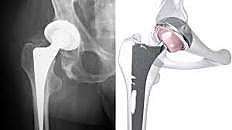

• artroplastia de baja fricción

artroplastia de baja fricción

Sir John Charnley, en compañía de Feagin: incluyeron conceptos como: alteración quirúrgica de la biomecánica de la cadera, lubricación, materiales, diseño

En cuanto al abordaje. una amplia exposición lateral con osteotomía del trocánter mayor, Tenotomía de aductores y psoas